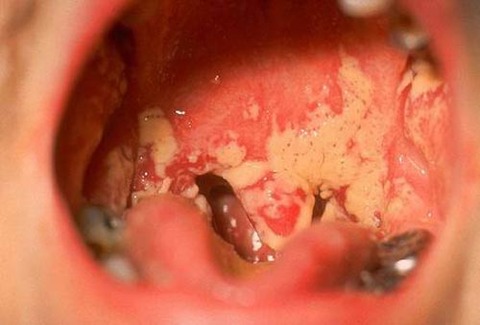

benh-lau-o-mieng-hong

Bệnh lậu là một bệnh lây lan qua những đường tình dục (STD) vì nhiễm vi rút vi khuẩn lậu. virus này thường hay thấy ở cổ tử cung, tử cung, ống dẫn trứng tại chị em cùng với lỗ sáo của nam giới. vi rút song cầu khuẩn cũng có khả năng gây nhiễm trùng tại niêm mạc miệng, vòm họng, mắt và trực tràng.

những dấu hiệu nhận biết viêm nhiễm trực tràng ở tất cả mọi người có nguy cơ bao gồm tiết dịch, ngứa hậu môn, đau tức, xuất huyết... nhiễm trùng trực tràng cũng không có biểu hiện. viêm nhiễm họng có thể dẫn đến đau họng song thường không thấy các dấu hiệu.